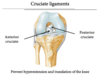

ACL tear

(Anterior cruciate ligament)

Results from twisting bones of knee in opposite directions